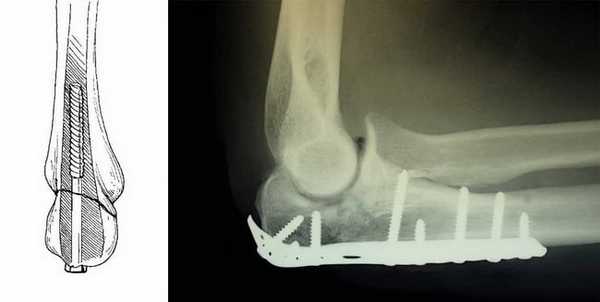

Наилучшим методом лечения внутрисуставного перелома локтевого отростка, позволяющим сохранить движения в суставе - это остеосинтез (устранение смещения и фиксация отломков металлоконструкцией). Операцию выполняют сразу после поступления пациента. Это ускорит реабилитацию и позволит сохранить полный объем движений в локтевом суставе. Локтевой сустав очень капризный в плане реабилитации. Если иммобилизация продолжается 4 недели и более, то практически во всех случаях у взрослых пациентов развивается контрактура.то есть движения ограничены на всю жизнь. Если перелом локтевого отростка произошел одним фрагментом, то возможна классическая операция, одна из самых простых и надежных методик - остеосинтез локтевого отростка по Веберу. Выполняется она при помощи двух титановых спиц и титановой проволоки.

В случае оскольчатого перелома со смещением и отрыве верхушки отростка локтевой кости, выполняют фиксацию осколков специальной титановой конструкцией, восстанавливая целость локтевого отростка и суставной поверхности локтевой кости.

Для фиксации травмированной кости используют следующие методы:

• Ортез или гипсовая повязка (лонгет);

• Титановая пластина с винтами для фиксации (операция);

• Винты без дополнительного удерживающего элемента (операция);

-Фиксация спицами и стягивающей петлей (остеосинтез по Веберу).

Открытая репозиция и внутренняя фиксация. Это наиболее распространенный метод лечения переломов локтевого отростка. Во время такой операции костные фрагменты сопоставляются друг с другом и фиксируются в нормальном положении винтами, проволокой, спицами или металлическими пластинами.

Ниже представлены некоторые наиболее часто применяемые методы фиксации локтевого отростка.

Фиксация перелома локтевого отростка спицами и стягивающей проволочной петлей

(Слева) Для фиксации перелома локтевого отростка можно использовать один винт, который вводится в костномозговой канал. (Справа) Фиксация перелома пластиной и винтами.